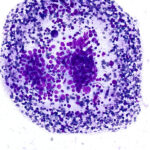

Slide Quality

Our propriety monolayer preparation ensures minimal cellular overlap, giving a clear view of cellular features. Every slide looks expertly done—even without the expertise.

Consistent Results with ASP vial technology

Each FNA pass is placed into a propriety ASP vial and homogenized, ensuring the slide is always representative of the cell block. Control the volume of the sample for ROSE and preserve the rest for the cell block.